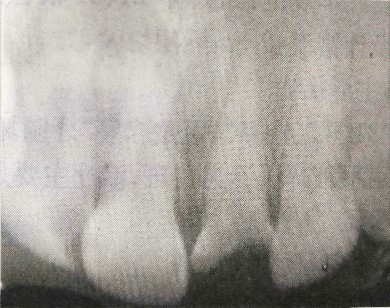

檢查:21牙冠缺損,黑褐色,根管口暴露,覆蓋污穢物,探診(-),冷測(cè)(-),叩診(+)。左上1唇側(cè)牙齦根尖部有白色瘺管出現(xiàn)。X線片檢查提示:21根尖區(qū)低密度影。全口牙齦紅腫,探診后出血,且下頜后牙區(qū)有附著喪失。相關(guān)情況請(qǐng)見(jiàn)下圖:

病例分析1

病例分析2

(3)X線檢查示21根尖部陰影。